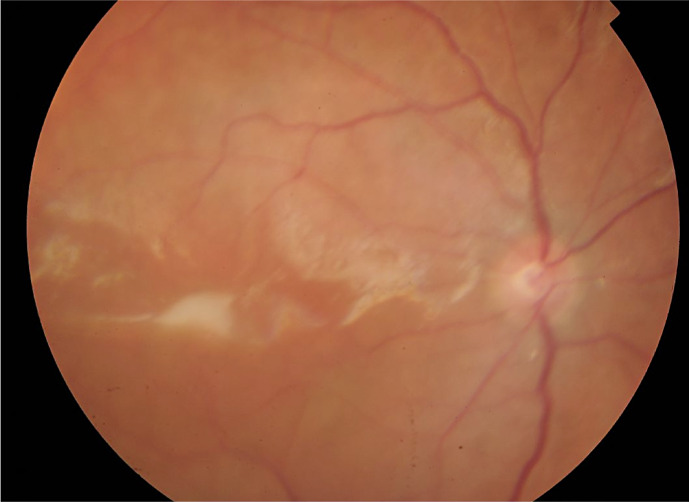

大量脉络膜上出血(SCH)是一种毁灭性的并发症,具有显著的发病率和不良的视觉和解剖结果。常规的处理方法是在手术引流前观察7-14天。然而,视网膜的永久性结构变化可能在这段时间内发生。脉络膜上注射重组组织型纤溶酶原激活剂(TPA)可加速血块分解,有助于早期手术引流。我们报告了一个病例系列,涉及黄斑块状SCH (MSCH)的早期引流辅助重组组织纤溶酶原激活剂(r-tPA)。病例介绍:回顾性分析3例累及黄斑的mscs患者,在出血后24小时内行脉络膜上r-tPA治疗,在注射r-tPA后48小时内早期引流,并联合玻璃体切除和填塞。所有患者均在初始损伤后24 h注射100µg重组TPA。注射r-tPA后6-48 h进行SCH引流。所有患者早期引流成功,视力均有改善。1例SCH复发,但再次成功治疗。结论:r- tpa辅助SCH早期引流技术是安全的,在恢复黄斑累及的mscs患者的视觉功能方面具有广阔的应用前景。我们的小样本表明,在出血24小时内注射100 μg/0.4 mL的r-tPA,可以在初次损伤后第2天手术引流SCH。需要更大规模的研究来进一步调查哪些患者可能从这种治疗中受益。

Introduction: A massive suprachoroidal haemorrhage (SCH) is a devastating complication with significant morbidity and poor visual and anatomic outcome. Conventional management is to observe for 7-14 days before surgical drainage. However, permanent structural changes in the retina can occur within this timeframe. Suprachoroidal injection of recombinant tissue plasminogen activator (TPA) may speed up clot breakdown and aid early surgical drainage. We present a case series of macula-involving massive SCH (MSCH) treated with early drainage aided by recombinant tissue plasminogen activator (r-tPA).

Case presentation: Retrospective case series of 3 patients with macula-involving MSCH treated with suprachoroidal r-tPA within 24 h of bleed and early drainage of SCH within 48 h of r-tPA injection, combined with vitrectomy and tamponade. 100 µg of recombinant TPA was injected into the SCH 24 h following initial injury in all patients. Drainage of the SCH was then performed 6-48 h after the injection of r-tPA. Early drainage was successful and visual improvement was seen in all patients. One patient had a recurrence of SCH but was successfully re-treated.

Conclusion: The technique of r-tPA-assisted early drainage of SCH is safe and has promising potential to restore visual function in patients with macula-involving MSCH. Our small sample would indicate that 100 μg/0.4 mL of r-tPA injected within 24 h of bleed allows surgical drainage of SCH as early as day 2 post initial injury. Larger studies are required to investigate further which patients are likely to benefit from this treatment.